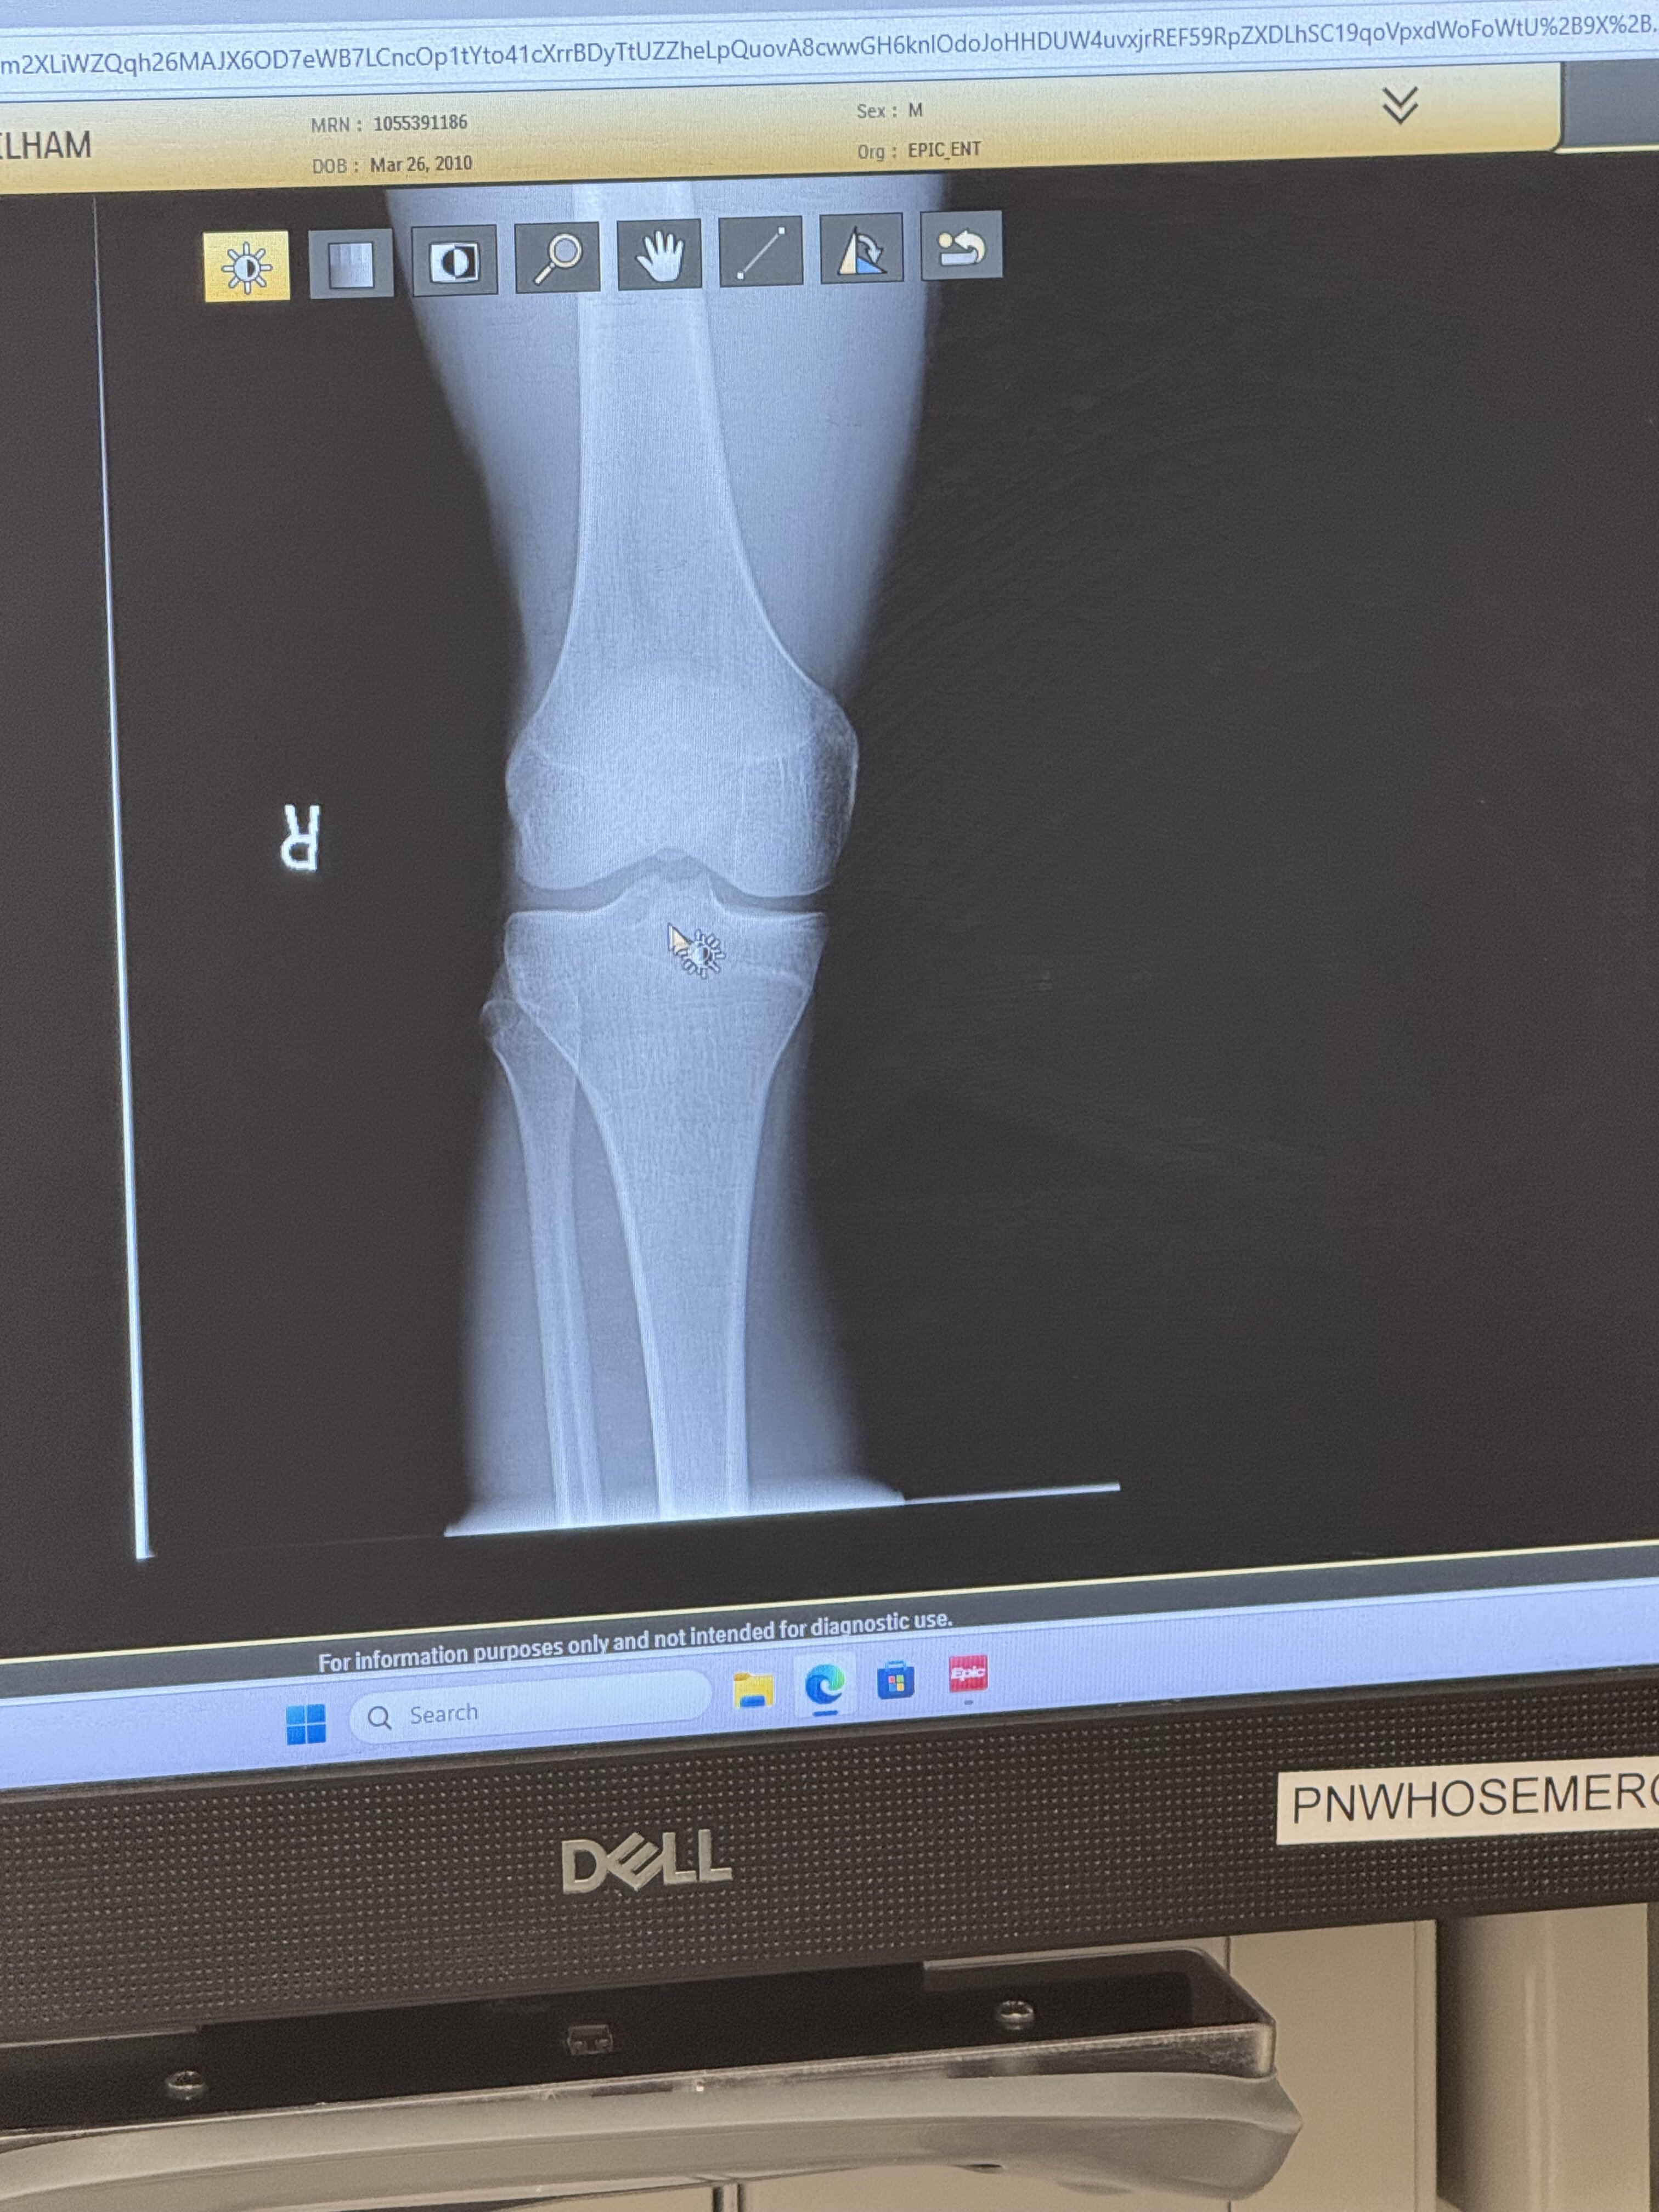

Are my growth plates closed? I’m planning on taking anastrozole

still opened, its so clear as well, what a retarded doctor

they're open, by the way.

How long u think i got?